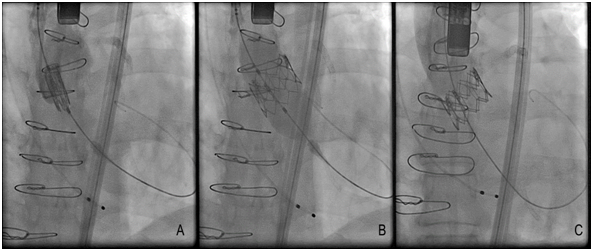

Until this moment, the TAVR devices approved and non-approved are described in (Table 1), and some TAVR devices have their fluoroscopic view demonstrated in (Figure 2). There was a recent report about Lotus valves recall due to pin troubles, following reports of problems with the device’s locking mechanism. The problem, according to the company, is the premature release of a pin connecting the Lotus valve to the device’s delivery system. Boston Scientific expects to reintroduce the Lotus to Europe and other regions in the fourth quarter of this year (2017).20 The most patients considered for TAVR undergo multimodal imaging assessment of the aortic root. The multislice computed tomography and/or three-dimensional echocardiography are the imaging modalities of choice (according to availability and local expertise) to evaluate the annular dimensions (diameters, area, perimeter) and unique anatomical features of each patient. A variety of adverse anatomical features may complicate TAVR procedure, and in such cases the availability of multiple TAVR technologies can facilitate the procedure safety.21

Figure 2: Fluoroscopic views of TAVR device after implantation A, Boston Lotus B. Medtronic Core Valve (Images of our own files of cases).